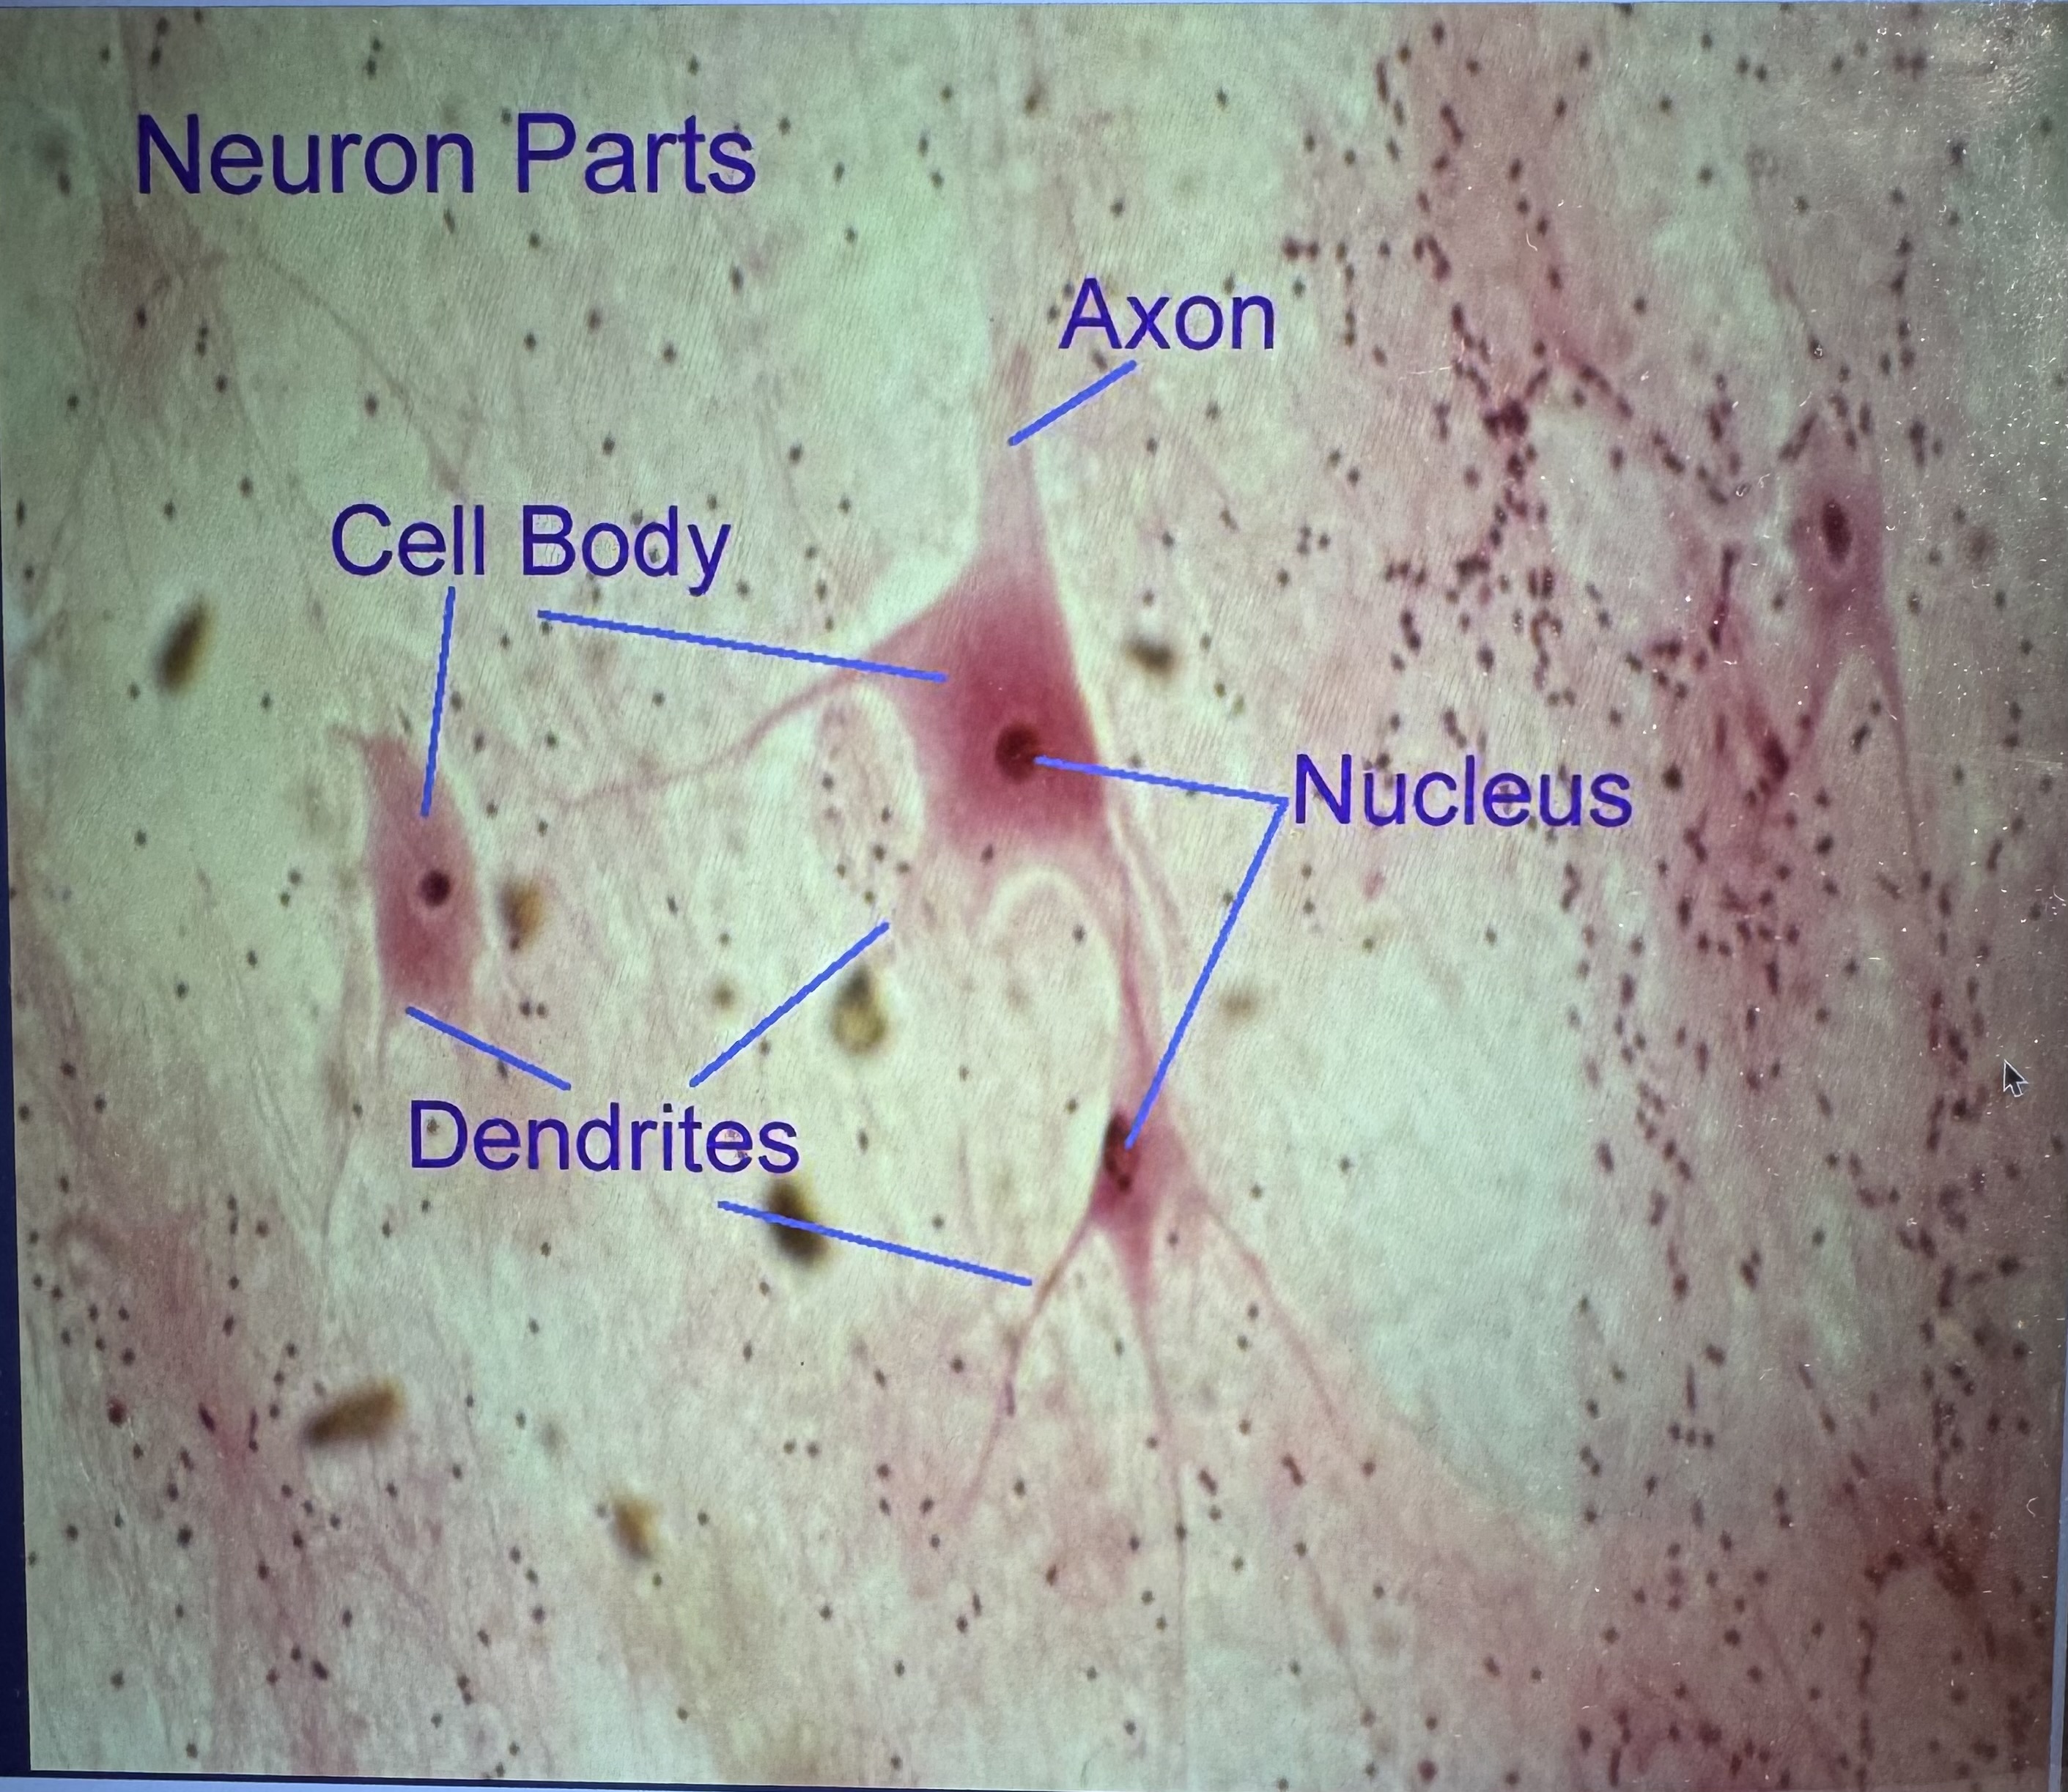

Neuron Histology